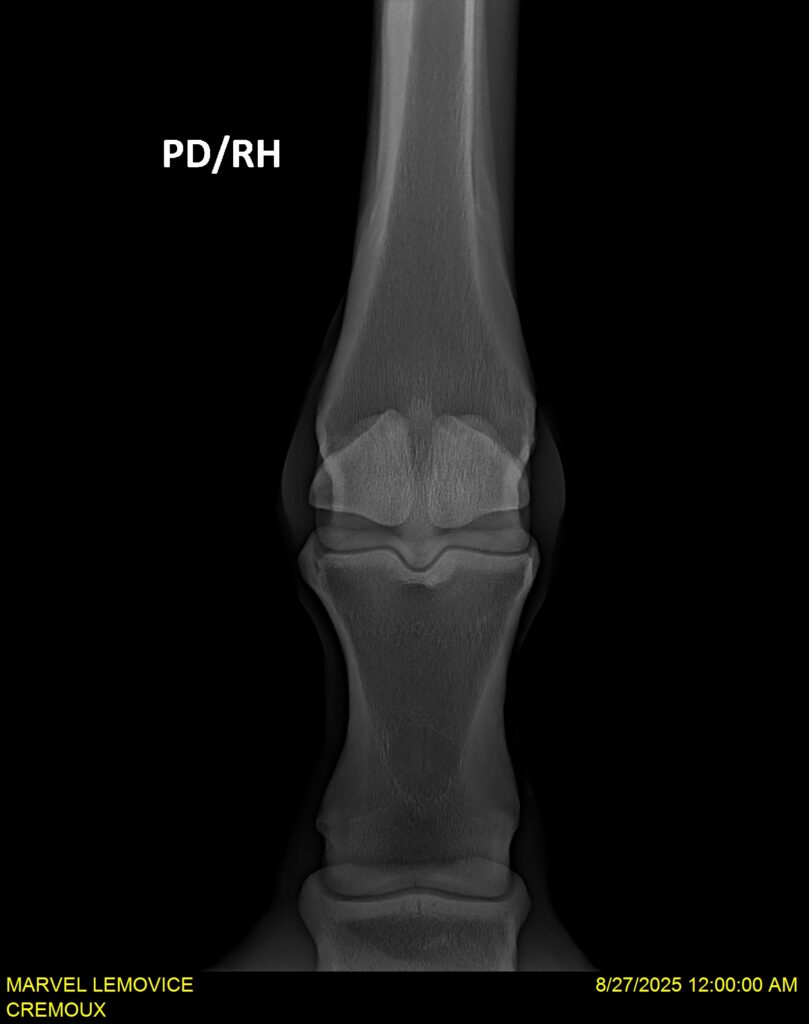

MARVEL LEMOVICE, hongre, Selle Français prend 4 ans en 2026. POPSTAR LOZONAIS x ROSIRE sur une excellente souche maternelle de l’élevage PLATIERE. Débourré aux trois allures et mise en route à l’obstacle. Super modèle avec du cadre et de la force, cheval respectueux avec des moyens. Très agréable au quotidien. Transport OK, maréchalerie OK, santé RAS, Bilan 20 clichés radios + clinique OK.

RADIOS ET CLINIQUE